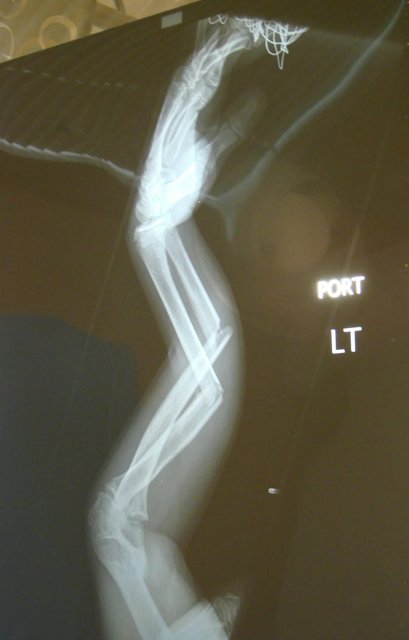

''2008 yılında kolumu kırdığım zaman çektirdiğim röntgeni buldum, eklemsiz gibi duruyorum.''

Kaynak: Reddit